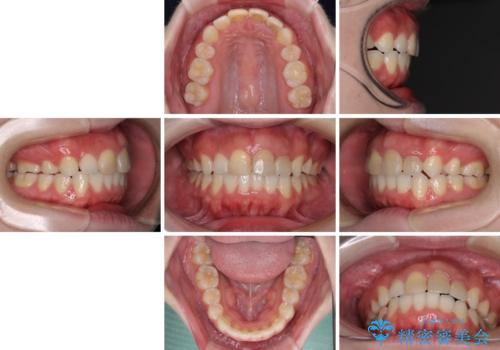

抜歯矯正の後戻り インビザラインによるオープンバイトの再矯正

上下前歯のオープンバイトを改善するため、インビザラインにて治療を行うこととしました。

外食が楽しみである患者様だったので、インビザラインによる治療期間は我慢の時期であったようです。

自己管理を徹底していただいたので、1年程度で治療を終えることができました。